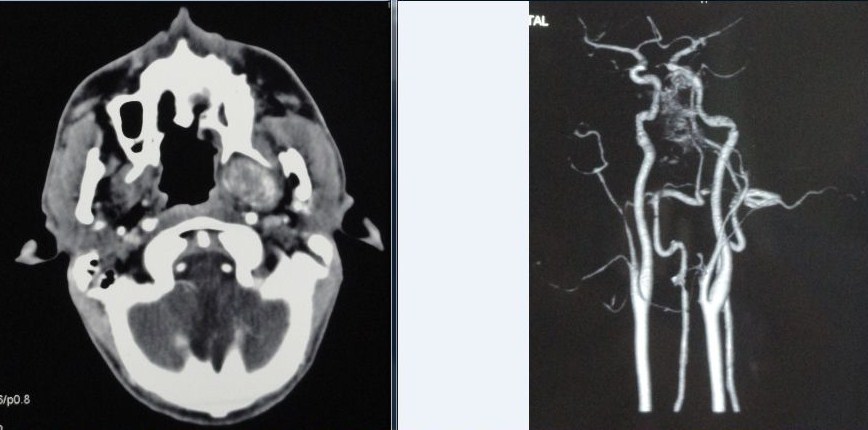

Imaging Tips:Cervical Adenopathy

- Regardless of lymph node size, most reliable imaging finding of metastatic disease is presence of central nodal necrosis on contrast-enhanced CT

- Nodes in jugulodigastric region (level II), or submandibular triangles (level I) with greater than 1.5 cm in maximum diameter, or node greater than 1 cm in maximum diameter elsewhere in neck, are considered likely to contain metastatic carcinoma

- In general, nodal enhancement seems to imply increased nodal vascularity, most common causes are acute infections

- Nodal calcification can be seen in metastatic nodes (papillary thyroid cancer, metastatic adenocarcinoma from lung, breast and gut) but may also be seen with tuberculosis, healed necrotic, abscessed nodes, amyloidosis